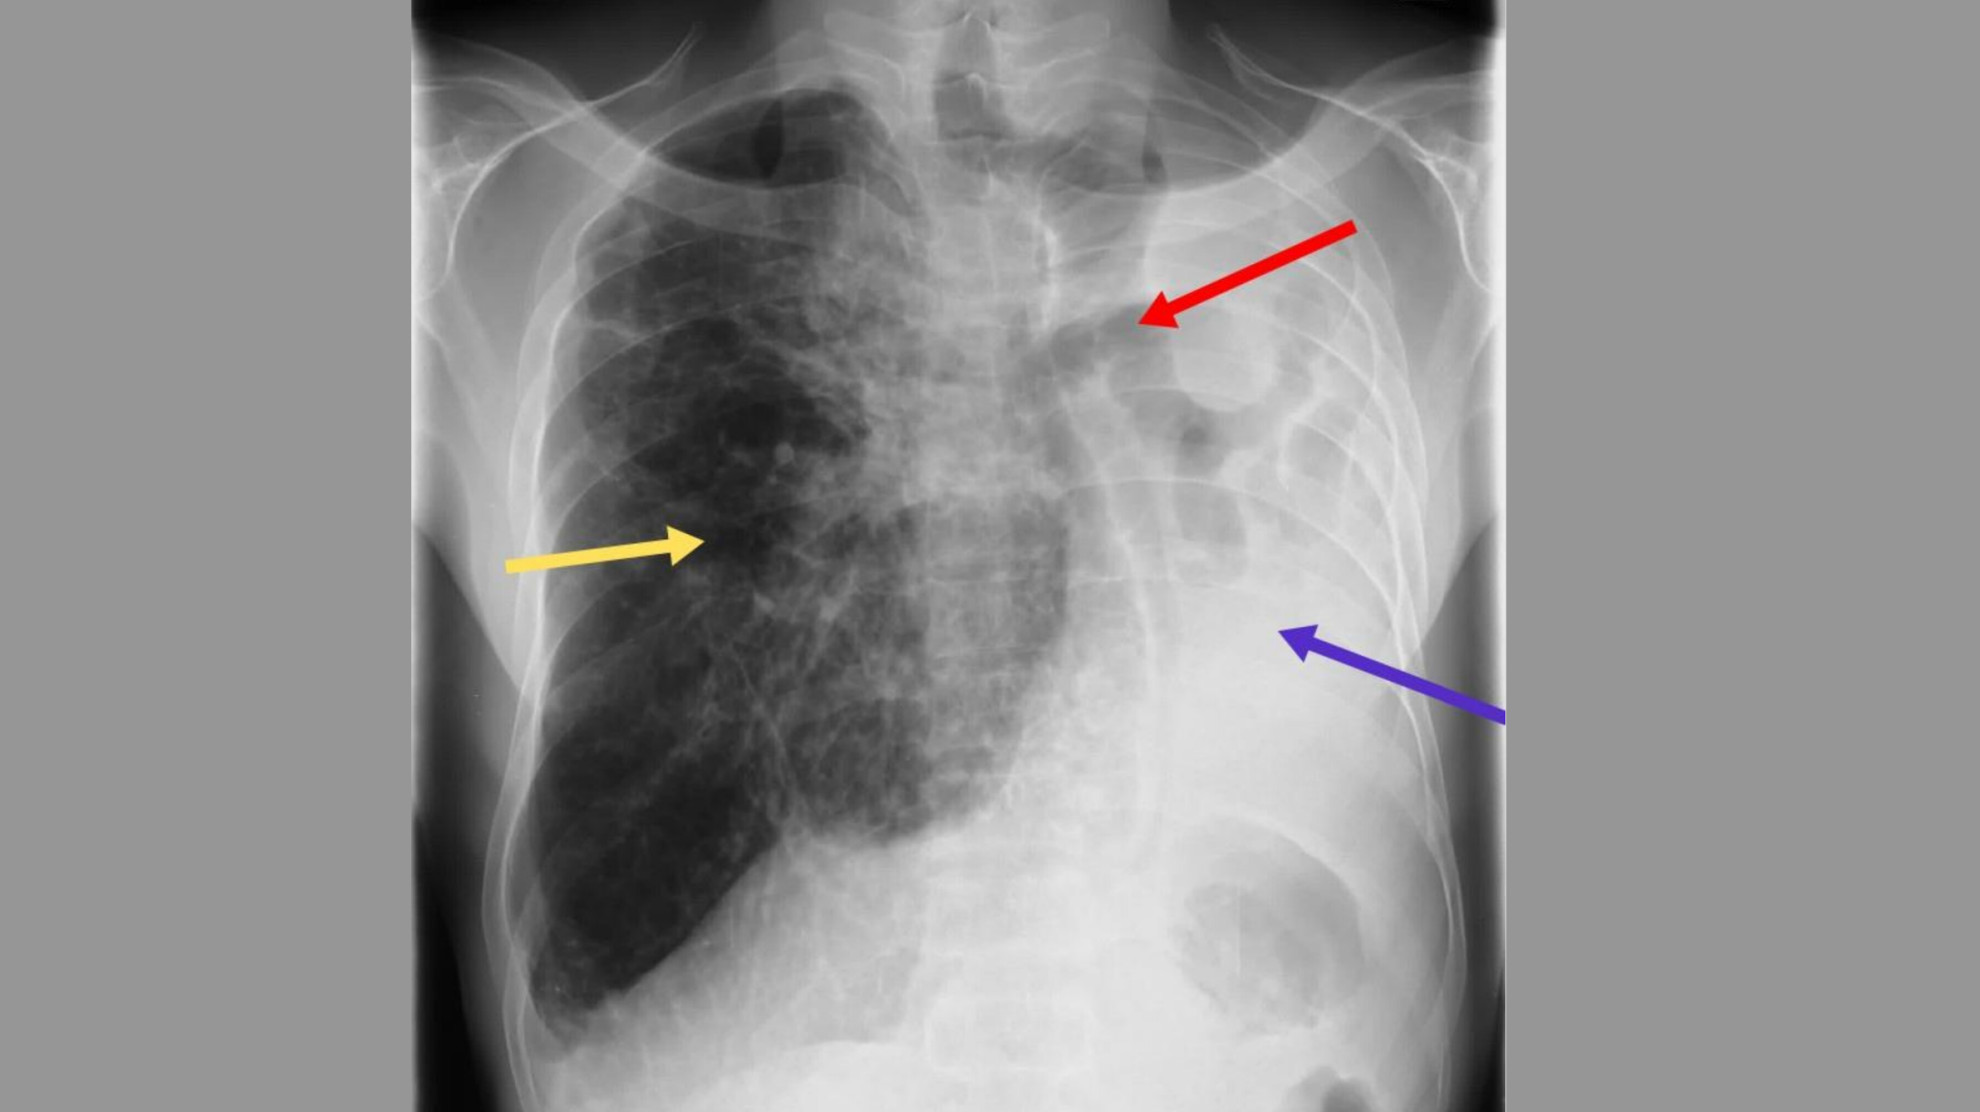

Рентгенограмма грудной клетки показала значительное уменьшение объема левого легкого, существенное смещение средостения влево, стеснение ребер с левой стороны и компенсаторную гипервентиляцию правого легкого.